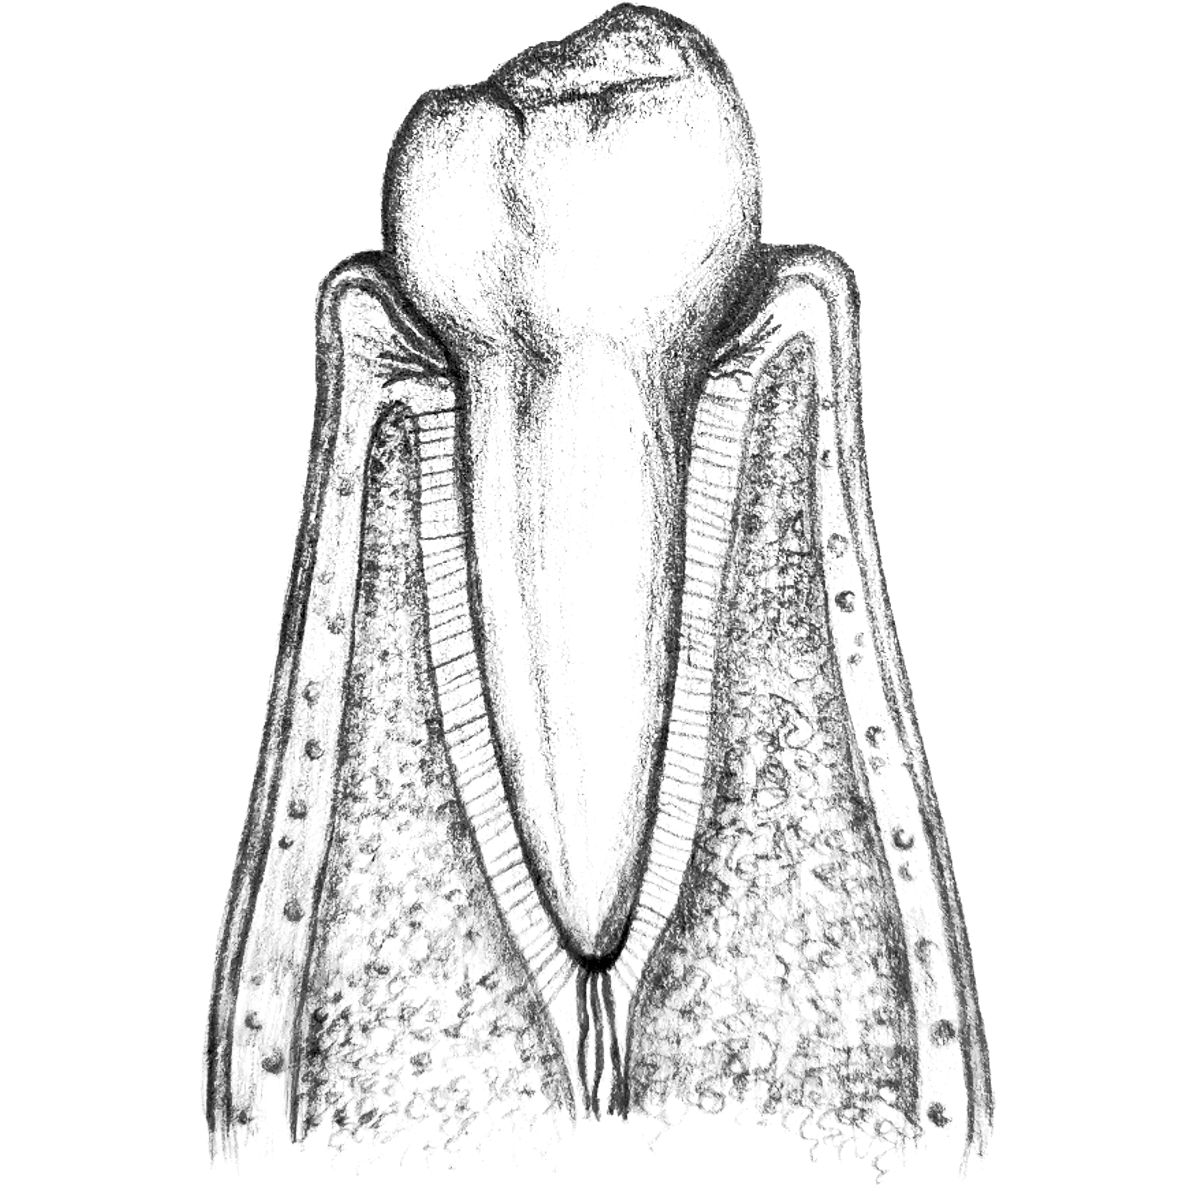

Patienten mit freiliegenden Zahnhälsen klagen außerdem häufig über eine erhöhte Schmerzempfindlichkeit gegenüber Kälte und Hitze. Weitaus gravierender: Ist das Zahnfleisch zurückgegangen, liegen die Zahnhälse frei. Sie sind anfälliger für Kariesbakterien, da der Zahnschmelz dünner ist als an der Zahnkrone. Zahnfleischschwund kann im schlimmsten Fall dazu führen, dass die Bakterien den Kieferknochen befallen, mit der Folge, dass die Zähne nicht mehr fest sitzen und ausfallen können.